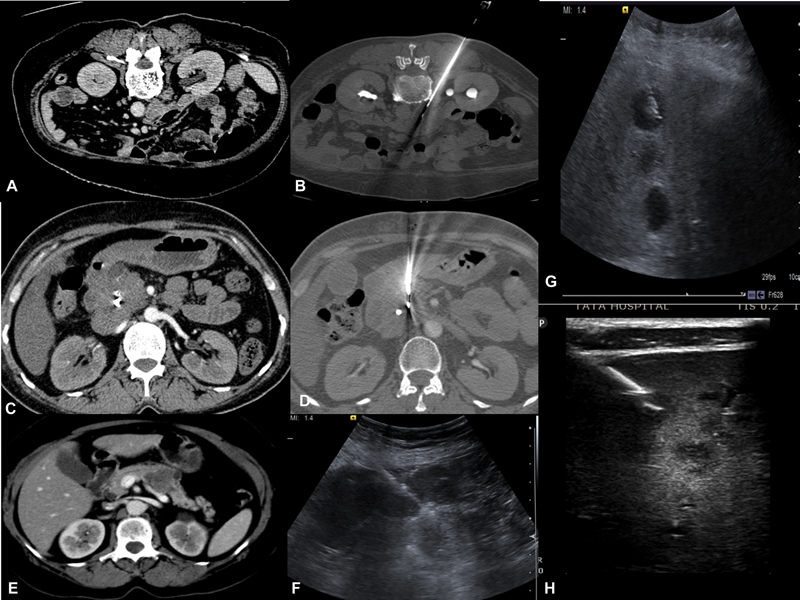

C)Abdominal and pelvic lesions-Soft-tissue masses involving the peritoneum, omentum, retroperitoneal nodes, and mesenteric lymph nodes are amenable to percutaneous biopsies under USG or CT guidance depending on size and location. Liver biopsies are done under USG guidance; however, CT guidance can be preferred when there is difficulty in visualizing lesions such as under the dome of the diaphragm. In certain cases, a combination of modalities can be used where both USG and CT scan can be used for lesions near para cardiac location[7] or navigation/fusion techniques with USG guidance can be done ([Fig. 2]).

| Figure 2:(A-B) Left Paraspinal approach for biopsy of the aortocaval lymph node. (C-D) CECT reveals pancreatic head mass where biopsy is performed via transgastric approach.(E-F) CECT reveals pancreatic body mass, USG guided biopsy of pancreatic mass with compression of bowel loops. (G-H) USG guided liver lesions biopsy traversing normal liver parenchyma. H-Lesions appreciated by using high-frequency probe.

| Figure 2:(A-B) Left Paraspinal approach for biopsy of the aortocaval lymph node. (C-D) CECT reveals pancreatic head mass where biopsy is performed via transgastric approach.(E-F) CECT reveals pancreatic body mass, USG guided biopsy of pancreatic mass with compression of bowel loops. (G-H) USG guided liver lesions biopsy traversing normal liver parenchyma. H-Lesions appreciated by using high-frequency probe.